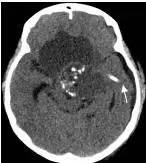

鉴于肿瘤体积超大,而且患儿间断出现意识障碍,直接作手术完全切除肿瘤的难度很大,为降低手术风险,所以我们采用先穿刺肿瘤囊减少肿瘤体积,降低颅压,二期手术争取完全切除肿瘤的策略。行肿瘤囊肿穿刺后,引流出约100多毫升囊液,肿瘤体积显著变小,见图3、图4。

图4.肿瘤囊穿刺手术后肿瘤体积减小

白色箭头示引流管